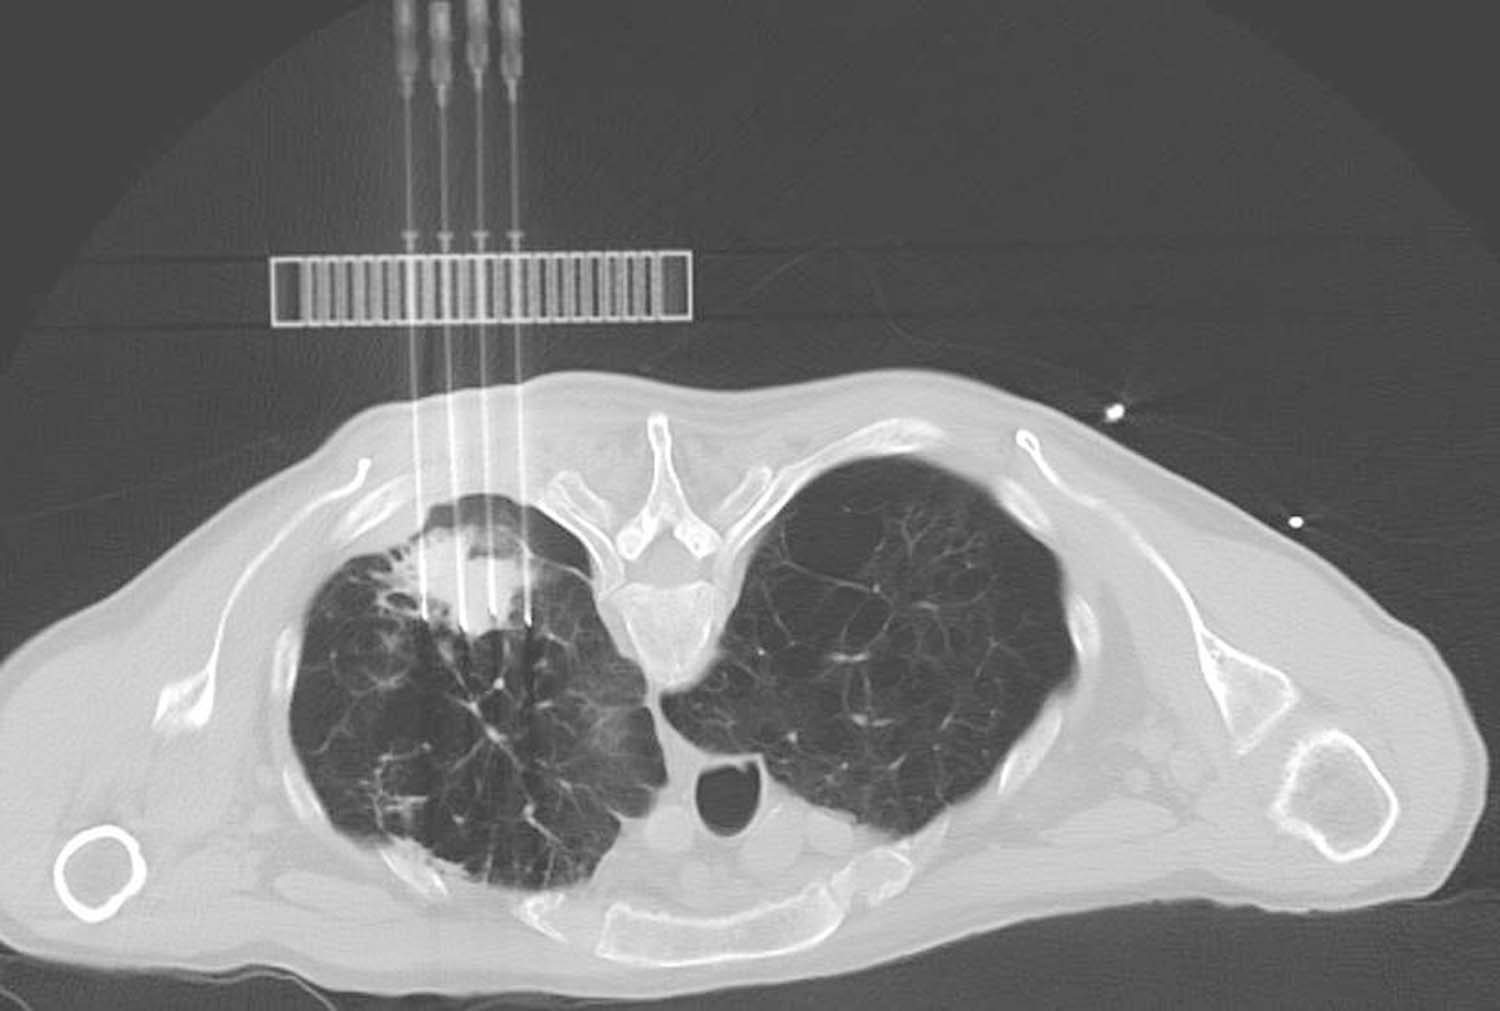

(5)术区消毒、麻醉成功后,在导航支架上安装穿刺模板,套无菌保护套,并使模板上的孔能够覆盖住穿刺区域,调整模板角度,并使用CT机上的激光线进行校正(图4-5-1)。

(6)行第二次CT扫描:其目的是确定定位固定针的进针位置与深度。选择在模拟进针点周边1~2cm的肋间,刺入定位固定针,即在肺内结节的周边刺入定位针,对结节周边局部肺组织起到固定作用(图4-5-2)。

图4-5-1 利用CT机上的激光线进行校正

图4-5-2 穿刺定位固定针